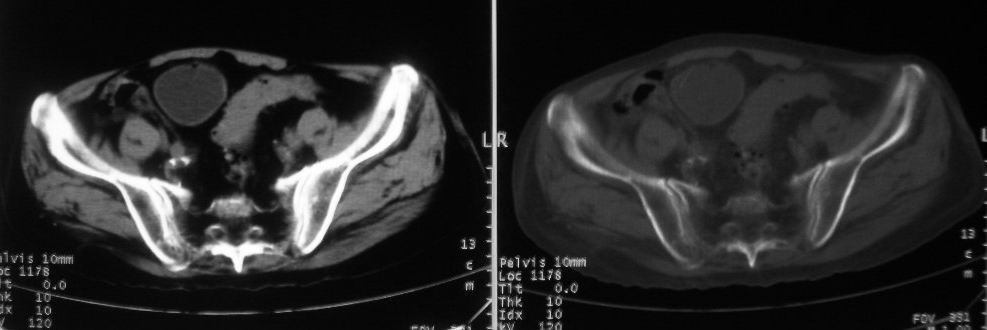

以下是引用深泽交通医院在2008-10-3 15:33:00的发言:[br]前列腺实性增大伴分叶状,与包膜间隙境界不清;椎体松质区间结节样密度影,考虑:前列腺癌,并椎体成骨性转移